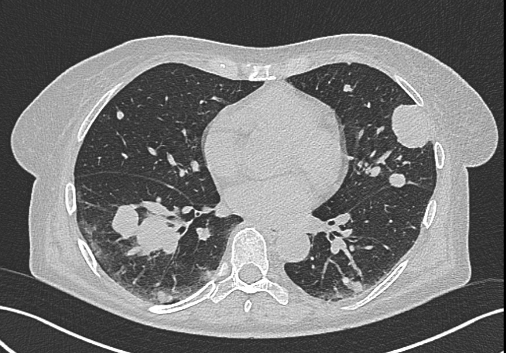

NO: 58letá žena, u níž byla na CT zjištěna objemná vaskularizovaná expanze pravé ledviny 10x12 cm bez trombózy, bez lymfadenopatie. Poté na CT zobrazeny četné plicní metastázy velikosti do 4 cm a metastáza na rozhraní acetabula a kosti kyčelní vpravo. Pod CT kontrolou provedena biopsie nádoru ledviny. Jedná se o tumor pravé ledviny (12 cm) cT2b cN0cM1 (plíce, pravá kyčel).

/ Obr. č. 1-5: CT hrudníku, břicha a pánve, patrná expanze pravé ledviny, plicní metastázy, lytická metastáza v pravé kyčelní kosti.